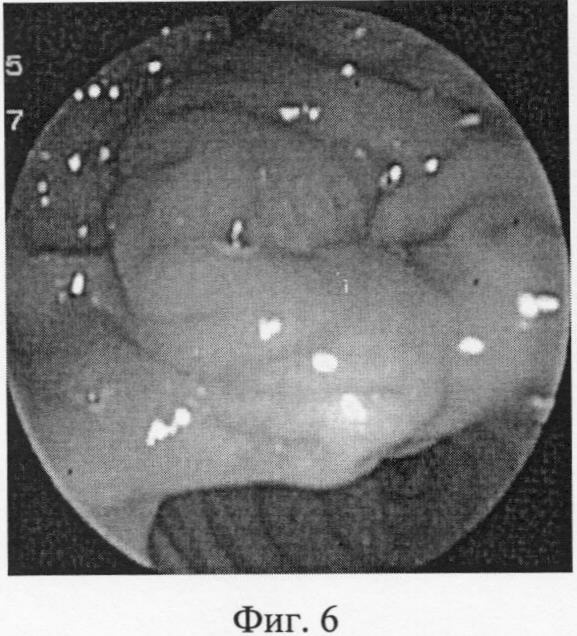

На эндоскопических фотографиях (фиг.6-12) наглядно представлены этапы операции эндоскопической папиллотомии предложенным новым нетипичным способом – крестообразным разрезом.

Фиг.6 – осмотр операционной зоны: БСДК уплощен.